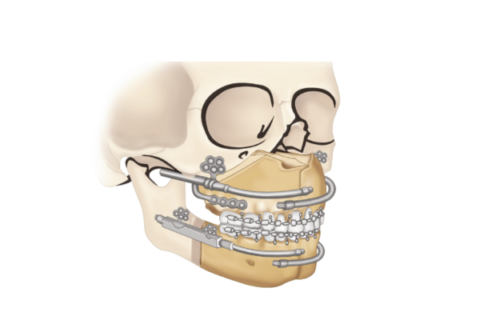

Distraction Osteogenesis

adual bone lengthening to correct facial deformities.